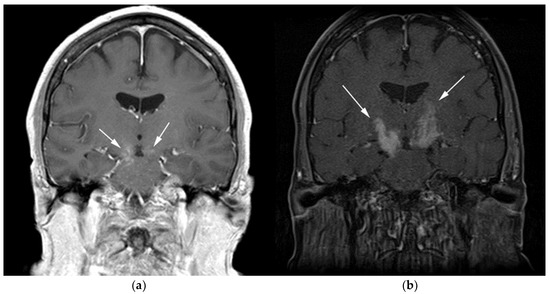

Figure 2.

A 64-year-old-woman presenting with rapid onset of memory deterioration and altered sensorium. (a) Coronal MRI T1 post-contrast images show subtle enhancement along bilateral deep nuclei. At this time, no diagnosis was determined. After 3 weeks, patient presented to emergency department with worsening symptoms. A follow-up MRI was performed. (b) Coronal MRI post-contrast fat-saturated images revealed progressive increase in extent of diffuse infiltrative enhancing masses (white arrows).

Figure 3.

Same MRI series. (a) Axial post-contrast MRI image shows lesions extending caudally to involve the bilateral superior cerebral peduncles and anterior aspect of the mid-brain. (b) Axial MRI T1 post-contrast fat-saturated images show involvement of the posterior limb of the internal capsule and the thalami bilaterally (white arrows). (c) Extension along the lateral aspect of the pons, dentate nucleus, and the middle cerebellar peduncles (white arrows). (d) Axial FDG fused PET/CT image shows increased activity in the aforementioned lesions. Additional hypermetabolic lesions are seen along the course of the corticospinal tract (white arrows). Imaging findings and pattern of involvement are consistent with lymphomatosis cerebri. (e) H&E section shows a tumor composed of large and pleomorphic cells with intermingled small lymphocytes. Primacy CNS lymphoma typically demonstrates an angio-centric predilection. (Original magnification 400×, H&E stain). Other differential diagnoses include a vasculitic process, toxic or metabolic encephalopathy, paraneoplastic syndrome, or acute disseminated encephalomyelitis. Biopsy showed a large non-cohesive B-cell lymphocyte population consistent with LC.